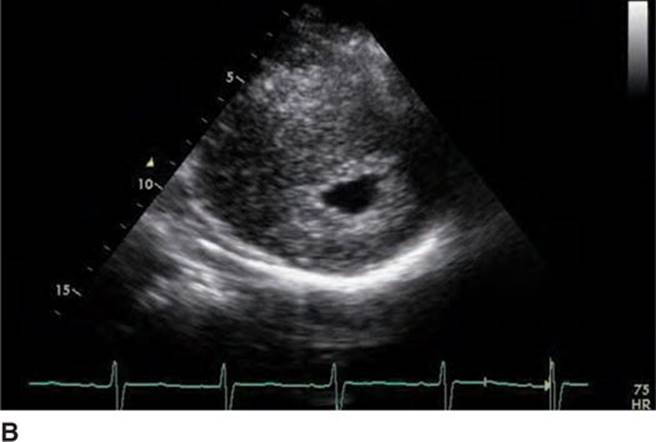

FIGURE 53-3A Parasternal short axis view of left ventricle in diastole.

FIGURE 53-3B Parasternal short axis view of the left ventricle in systole.